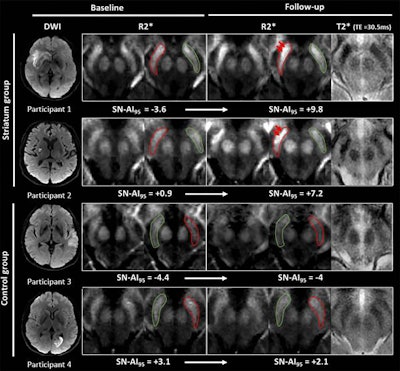

To test the efficacy of R2* mapping relative to assessing iron content and neurodegeneration, Linck and colleagues consecutively enrolled 181 patients between June 2012 and February 2015. The participant group included 127 men and 54 women with a mean age of 64.2 years (± 13.1 years) who presented with suspected minor to severe supratentorial cerebral infarcts (75 striatum infarcts and 106 in other brain locations). The subjects were evaluated with diffusion-weighted MR imaging 24 to 72 hours after their event.

MRI scans were performed on a 3-tesla scanner (Discovery MR 750w, GE Healthcare) with a 32-channel phased-array head coil. The researchers used the same protocol for baseline and one-year follow-up imaging, which included diffusion-weighted imaging (DWI) and corresponding apparent diffusion coefficient values, 3D T1-weighted images, and 2D T2* multiecho fast gradient echo sequences. R2* maps were computed from multiecho T2*, followed by coregistration of all sequence maps to the native 3D T1 images.

At the one-year follow-up, the researchers found higher average R2* values within the substantia nigra after a supratentorial infarction, "a finding that we interpret as iron accumulation as a result of neurodegeneration," they wrote. In addition, R2* maps consistently showed higher substantia nigra R2* values (iron concentration) when the infarct occurred at the ipsilateral striatum compared with R2* values when the infarct occurred in other locations. In other words, R2* mapping of iron content also could be used to image neurodegeneration remotely, if strokes were to occur in disconnected areas.